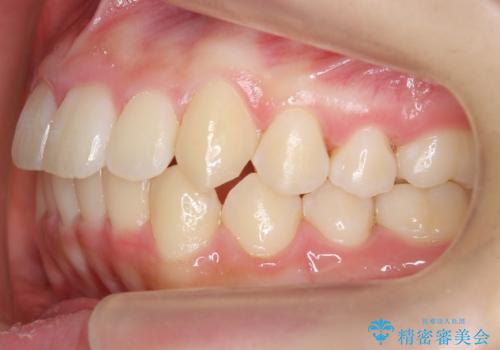

中学生のマウスピース矯正 歯を抜かずにキレイに

- 10代女子

- 矯正装置

- インビザライン フル

- 治療期間

- 1年11ヶ月

- 出っ歯を主訴に来院。

(1)インビザラインで歯を少し削って並べる。歯は抜かない。・・・歯を抜かなくて良い。歯磨きが楽、装置も目立たない。通院は3ヶ月に1回。

非抜歯ながらも、矯正用のインプラントを使用し、出来るだけ前歯を下げるように工夫して治療しました。

歯を抜かずに治療しましたが、治療前後で口元が悪化しないように治療することができました。